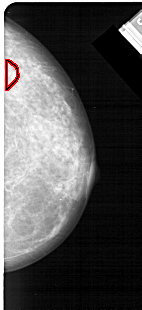

A_1473_1.LEFT_MLO

LEFT_MLO LINES 5476 PIXELS_PER_LINE 2221 BITS_PER_PIXEL 12 RESOLUTION 43.5 NON_OVERLAY

FILE: A_1473_1.RIGHT_MLO.OVERLAY

TOTAL_ABNORMALITIES 1

ABNORMALITY 1

LESION_TYPE MASS SHAPE IRREGULAR MARGINS ILL_DEFINED

ASSESSMENT 4

SUBTLETY 3

PATHOLOGY BENIGN

TOTAL_OUTLINES 1

BOUNDARY